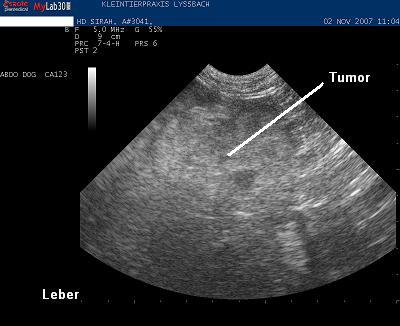

Die Untersuchung bestätigt, dass der Geschwulst von der Leber ausgeht. Die Leber ist weiträumig durchsetzt von grossen und kleinen Knoten von unterschiedlicher Echotextur und Echogenität. Dringender Verdacht eines Lebertumors (Leberkrebs).

Mit einer feinen Kanüle wird unter Ultraschallführung am wachen Tier eine schmerzlose sogenannte Feinnadelaspiration der Leber durchgeführt. Die Ausstriche werden in einem externen Labor von einem Pathologen untersucht. Er stellt die Diagnose eines „Hepatozellulären Karzinoms“. Dieser von der Leber ausgehende, bösartige Krebstyp befällt vor allem ältere Hunde und kann wegen fehlenden Krankheitssymptomen lange unentdeckt bleiben.